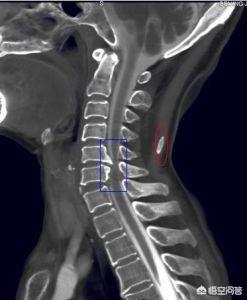

La compréhension de la spondylose cervicale remonte à quelques décennies. Les causes profondes de la spondylose cervicale sont aujourd'hui reconnues comme étant : les changements dégénératifs des disques cervicaux, le relâchement des corps intervertébraux et la production d'encombrements osseux (éperons osseux) sur les bords des vertèbres.), ou des ruptures et prolapsus discaux et d'autres symptômes causés par la compression des racines nerveuses, de la moelle épinière ou des artères vertébrales.

la discopathie dégénérative

Le disque intervertébral est, dans le corps humain, le plus précoce et le plus sujet aux changements dégénératifs avec l'âge, et il a une relation significative avec les contraintes et les traumatismes, ainsi qu'avec les habitudes de vie, la profession, l'état général ou le système endocrinien.

Un disque intervertébral normal contient 80 % d'eau dans le noyau pulpeux et 65 % d'eau dans l'anneau fibreux. Avec l'âge, la teneur en eau diminue progressivement, ce qui entraîne une perte graduelle de l'élasticité et de la résistance du disque.Bien entendu, lorsque le disque se rompt ou se prolabe, il contient moins d'eau, le disque est faible et perd son rôle de support du poids, l'espace intervertébral se rétrécit et, lorsque la colonne cervicale se plie, le corps vertébral se déplace incorrectement d'avant en arrière, ce qui provoque une instabilité intervertébrale.

Lorsque l'anneau fibreux est soumis à une pression anormale, telle qu'un gonflement, un désalignement, etc., le nerf peut être stimulé et renvoyé vers la branche postérieure, ce qui entraîne des douleurs cervicales et des épaules, des spasmes musculaires au niveau du cou et d'autres symptômes.

ostéophyte vertébral

Lorsque le disque intervertébral dégénère, il est faible, l'espace intervertébral est rétréci, le corps intervertébral est instable, il se produit un désalignement, cette activité tire sur l'annulus fibreux et les ligaments longitudinaux environnants, et tire davantage sur le bord du corps vertébral, ce qui peut provoquer une hémorragie sous-périostée, l'ossification mécanisée de l'hématome, qui peut produire des ostéophytes (éperons osseux).

Certaines études ont montré que les hernies dures comme les épines osseuses sont une cause fréquente de spondylose cervicale. Ces éperons osseux peuvent comprimer les racines nerveuses, la moelle épinière et les artères vertébrales environnantes et produire les symptômes cliniques correspondants de la spondylose cervicale.